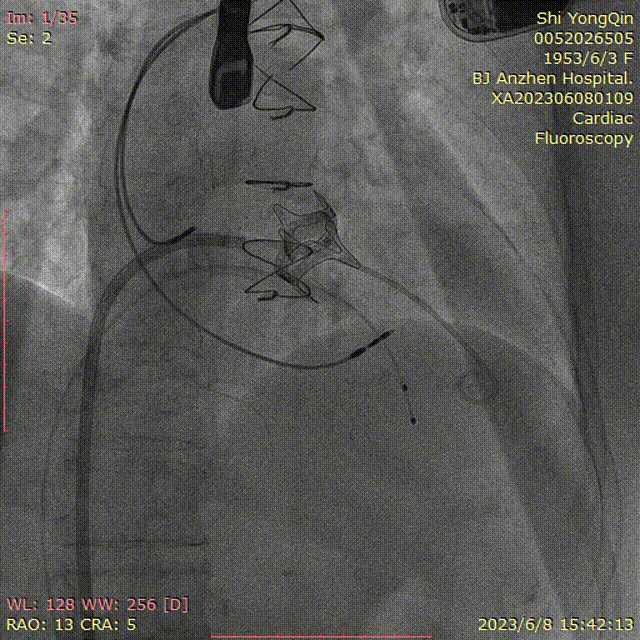

患者全麻,摆体位可寻找衰败生物瓣的切线投照体位,后消毒铺巾,穿刺双侧股静脉,左侧股静脉植入临时起搏器,右侧股静脉作为主入路,在超声指引下,按术前CT评估要求穿刺房间隔到达左心房,肝素化后(ACT>250秒),导入Agilis可调弯鞘管到达左心房,Pig造影导管跨过二尖瓣到达左心室心尖部,导入Safari导丝到达左心室;以12×40mm球囊扩张房间隔确认SAPIEN 3瓣膜可通过后,导入反向安装的23mm+3ml瓣膜到达下腔静脉,组装成功后,翻转其调弯系统后送入到左心房,跨过衰败的二尖瓣,在切线投照体位定位精确后,快速心室起搏下释放瓣膜,见瓣膜位置良好,超声显示无瓣周漏,测量左心室和桡动脉压差稍增高,超声显示LVOT流速稍增快;撤出瓣膜输送系统及导丝,撤出临时起搏电极,局部加压包扎,患者清醒后安返病房。

确认DSA投照体位

超声指引下房间隔穿刺

可调弯鞘指引下跨瓣

房间隔穿刺点扩张

球囊测试瓣膜的通过性

瓣膜导入

瓣膜的定位及释放

术后超声评估无反流